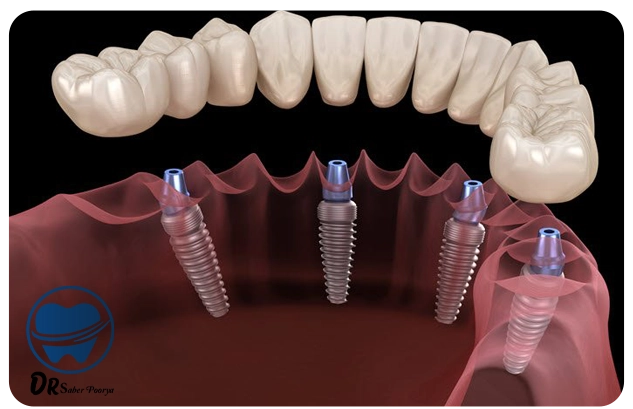

ایمپلنت دندان، به زبان ساده، یک پایهی فلزی کوچک است که به جای ریشهی دندان در استخوان فک قرار میگیرد و بعد از جوش خوردن با استخوان، تاج دندان مصنوعی روی آن نصب میشود.

مراحل انجام ایمپلنت؛ از مشاوره تا لبخند جدید

- قرار دادن پایه ایمپلنت در فک

- مدت زمان جوش خوردن (بین 2 تا 4 ماه)

- نصب روکش دندان

کل فرایند ایمپلنت معمولاً بین ۲ تا ۶ ماه طول میکشد. بعد از قرار دادن پایه فلزی در استخوان فک، مدتی زمان لازم است تا استخوان با پایه جوش بخورد (فرایندی به نام اسئواینتگریشن). بعد از آن، تاج دندان (روکش نهایی) روی پایه قرار میگیرد. البته در بعضی شرایط خاص، ایمپلنت فوری هم انجام میشود.

بله، در برخی موارد میتوان همزمان با کشیدن دندان، پایه ایمپلنت را هم در استخوان فک قرار داد؛ به این روش، "ایمپلنت فوری" گفته میشود. البته این کار فقط در شرایط خاص امکانپذیر است، مثلاً وقتی استخوان فک سالم باشد و عفونتی وجود نداشته باشد. دندانپزشک بعد از بررسی عکسها، تصمیم میگیرد که ایمپلنت فوری مناسب شما هست یا نه.